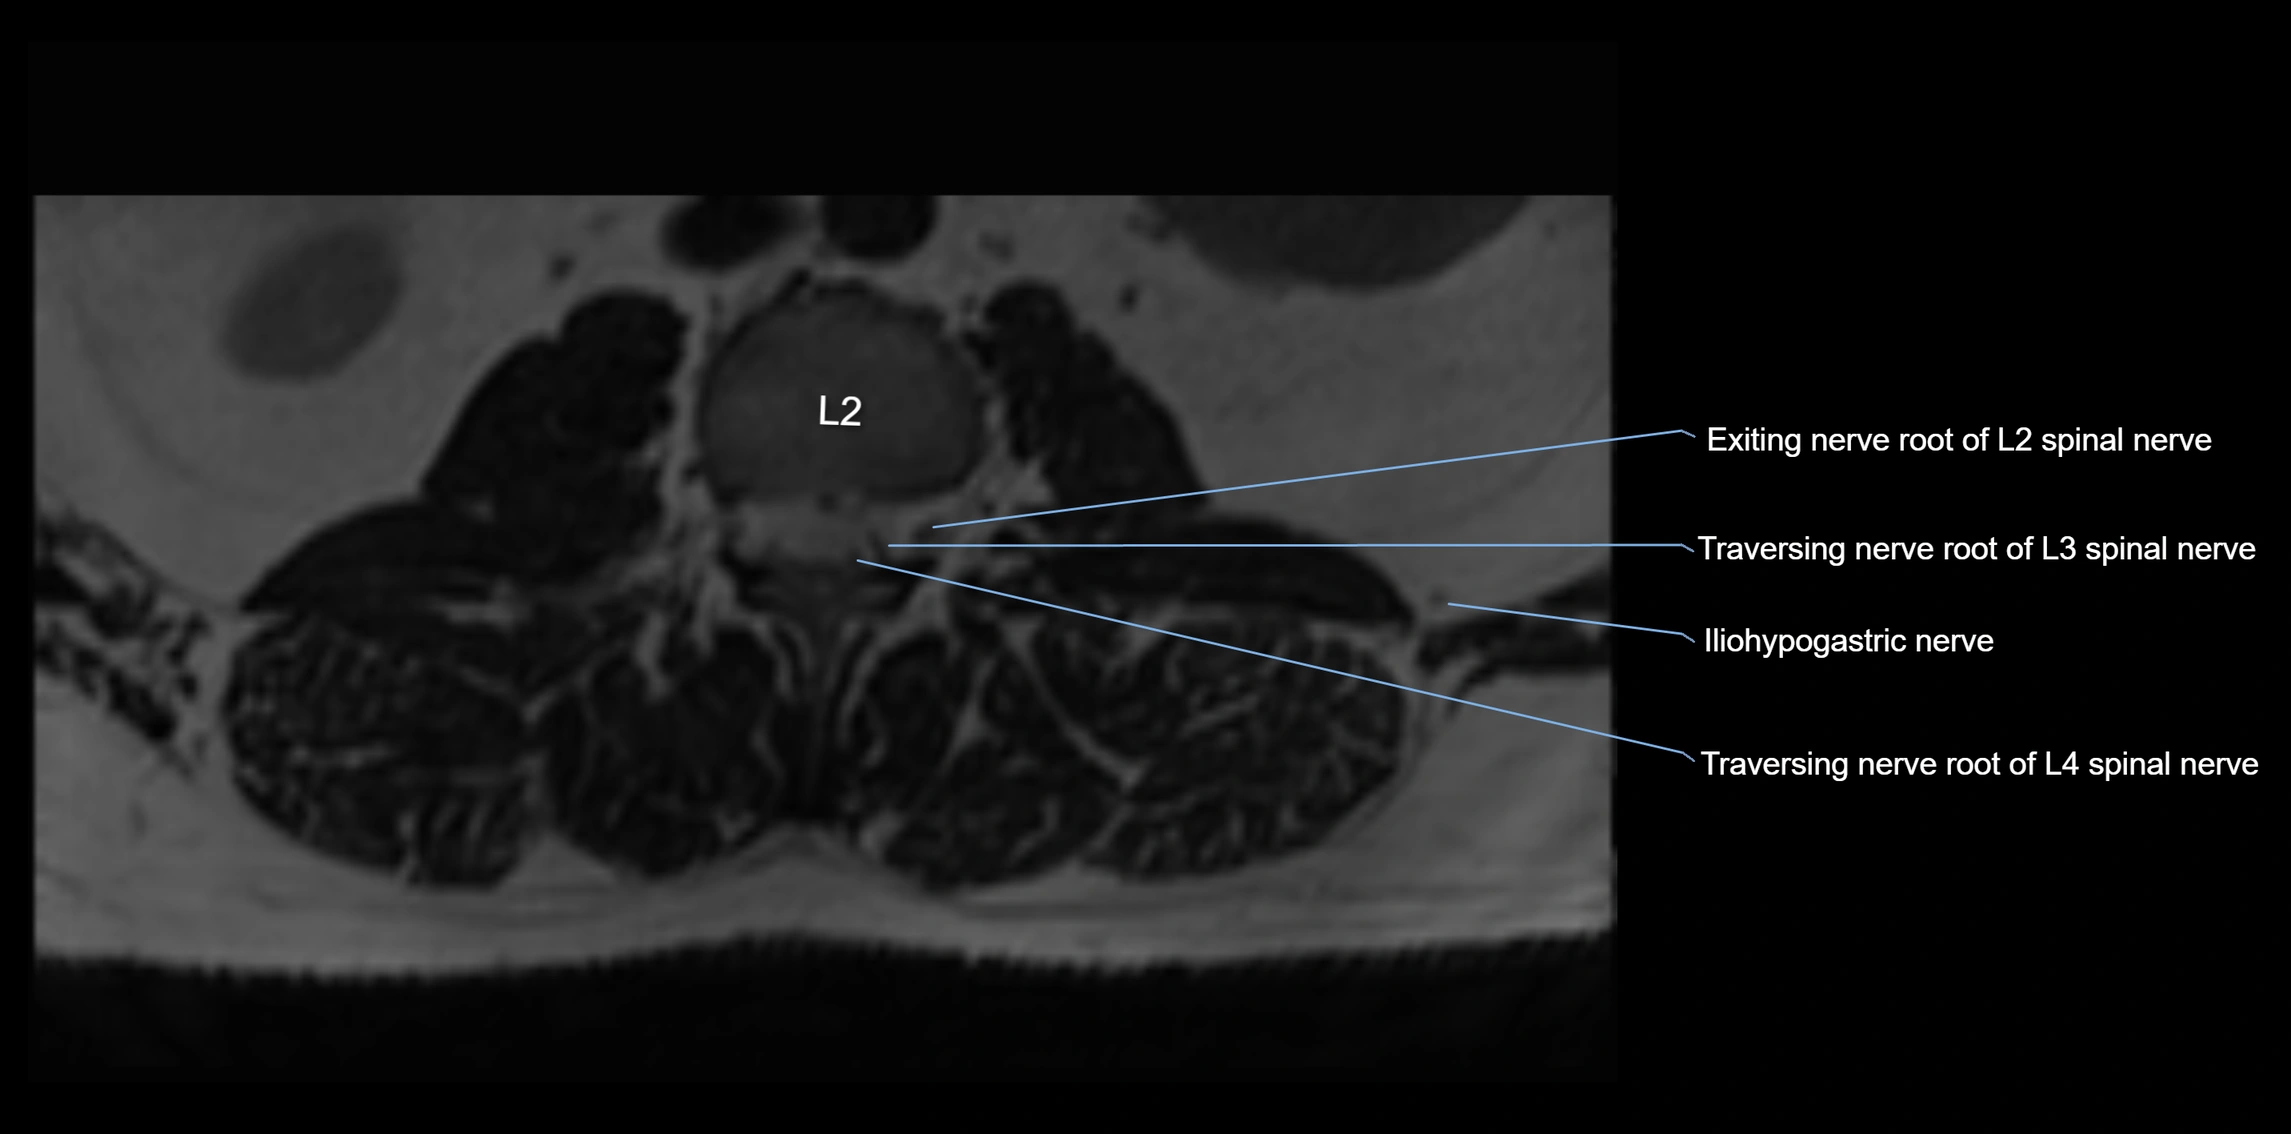

MRI Appearance

T1-weighted images:

• Nerve appears as a very thin low-to-intermediate signal intensity structure

• Surrounded by bright fat, aiding visualization

T2-weighted images:

• Nerve shows intermediate to mildly hyperintense signal compared to muscle

• Pathological involvement appears brighter

STIR (Short Tau Inversion Recovery):

• Normal nerve appears dark

• Inflamed or entrapped nerve appears bright hyperintense

T1 Fat-Sat Post-Contrast:

• Normal nerve enhances minimally

• Pathologic nerve (neuritis, entrapment, tumor infiltration) shows focal or diffuse enhancement

3D T2 SPACE / CISS:

• Nerve appears intermediate to mildly hyperintense compared to muscle

• Surrounded by bright fat or CSF, improving visualization

• Best sequence for mapping small pelvic nerves such as the anococcygeal